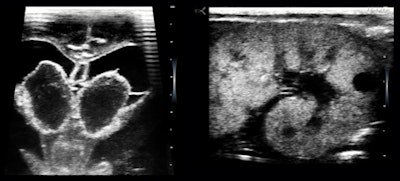

Figure 4: 7.8-week embryo.The clinic does not see pregnant women, but there were a few unexpected but very joyous first-trimester surprises (figure 4).

Vaginal bleeding seemed to be a pretty common presenting complaint, and even the first few cases included examples of the range of causes separable by ultrasound: polyps (figure 5a), endometrial hyperplasia, and adenomyosis.

The polyp case was a woman with a three-year history and no diagnosis. The adenomyosis patient had heavier bleeding for almost the same length of time and was deathly pale when she presented during a clinic "ultrasound day"; anemia did not seem to have been a clinical consideration. The endometrium was reduced to a thin, denuded basal layer in another woman with a month of bloody flow (figure 5b).

I am including this case because it reminded me of a clinical pearl: Whenever you have vaginal bleeding without an ultrasonically visible cause, think of clotting disorders such as von Willebrand disease.

Figure 5a and b: A long-axis view of a retroverted uterus with stalked polyps and perhaps a touch of adenomyosis, and a transverse image of a normal fundal endometrium.'Incidental' findings

Figure 8: 27-week preemie with bilateral germinal matrix hematomas and polycystic kidneys.The NICU is brimming with the most highly educated, proficient, and hardworking talent in the medical world. I have always felt that neonatologists should be scanning their own patients and that they should be able to look whenever they thought it might alter their management plans. When I used the U-Lite, I was interacting directly with neonatologists who intimately knew the babies I scanned, so we could go directly to the issues of immediate medical concern.